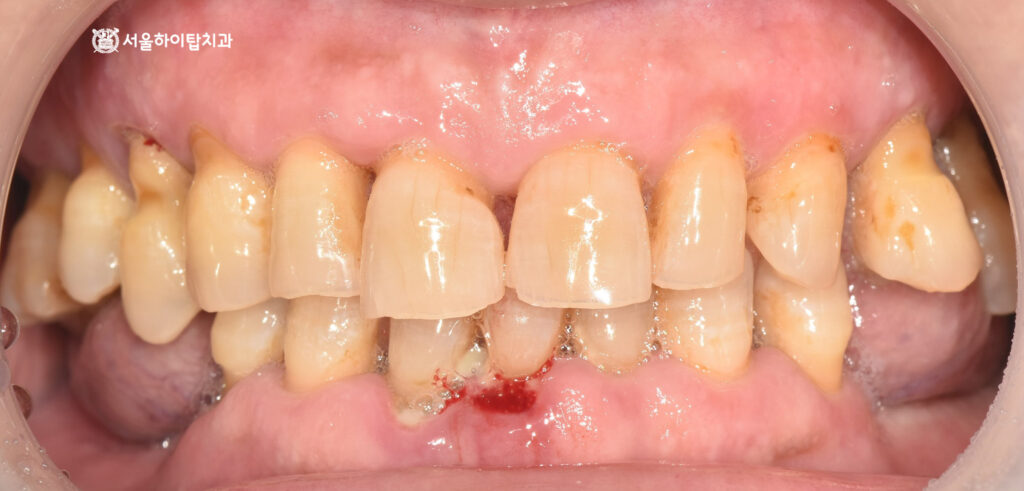

이어서 구강 내 모습을 살펴보면,

주안동 치과 에서는 곳곳에 치태와 플라그가

쌓여 있는 것을 확인할 수 있습니다.

특히 화살표로 표시된 교합면에서는

심한 마모가 관찰되는데,

이는 앞서 상실된 어금니 때문에

전치부(앞니)로 음식을 저작했을

가능성을 시사하는 소견입니다.

이처럼 비정상적인 저작 패턴은

마모를 가속화할 뿐만 아니라,

장기적으로 자연치 구조와

치은 건강에도 영향을 미칠 수 있습니다.

입을 다물었을 때 보는

측면, 정면 사진에서도

정출되어 치근이 보이는 모습과

출혈, 잇몸 부종, 전치부 마모 등

전형적인 심한 치주염의 양상을

보여주고 있습니다.

빠른 치료가 요구되는 상황입니다.